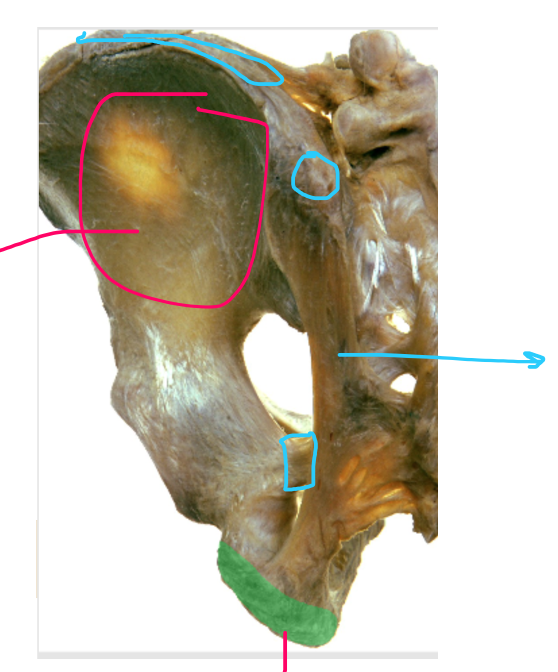

label the pelvis diagram

label this diagram

label this image: hip lateral/external rotators

label the diagram